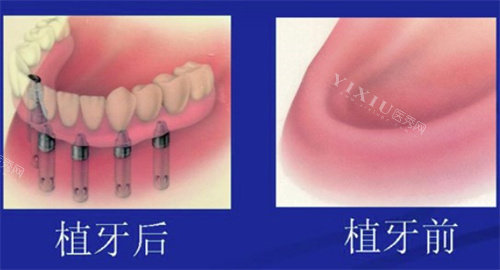

替代技术成熟:

吸附性义齿、全瓷冠桥等修复技术生物相容性与舒适度显著提升,费用仅为种植牙的1/3至1/5。

智能化即刻负重义齿技术使患者在24小时内完成修复,避免了种植牙3-6个月的治疗周期。

对于牙槽骨条件差、高龄或患有全身性疾病的患者,可优先考虑传统假牙或桥接修复。